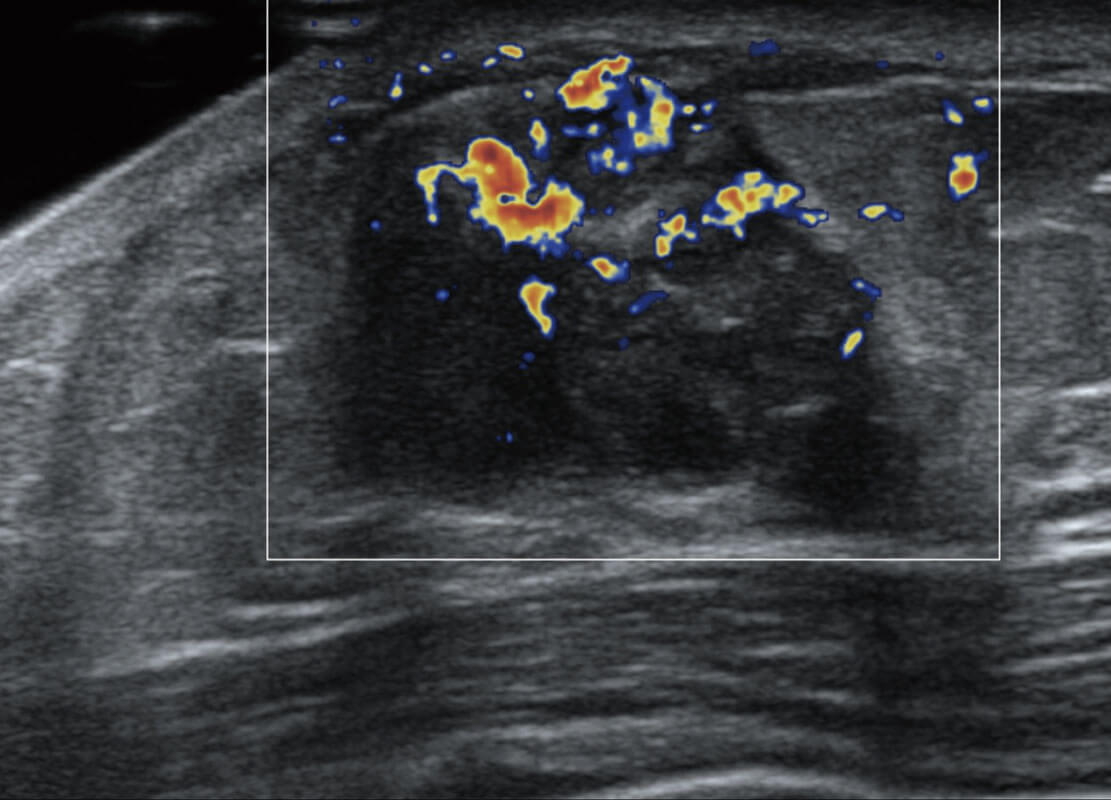

乳腺超声 / 新生儿

P60搭载宽频带线阵探头、宽景成像、弹性成像技术,为您提供乳腺应用方案。P60支持高频相控阵探头、线阵探头、腹部高频探头、腹部微凸探头等,丰富的探头群搭载敏感的彩色血流成像,适用于新生儿多种脏器检测要求,满足新生儿筛查需求。

• 乳腺癌显微血流